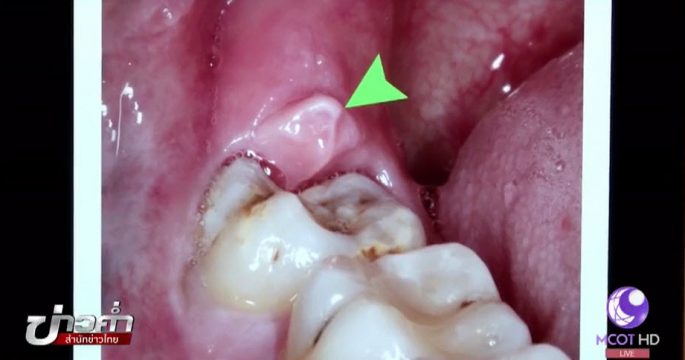

บนสังคมออนไลน์แชร์เตือนกันว่า การผ่าฟันคุดนั้นอาจจะทำให้เป็นอัมพาตได้ เรื่องนี้จริงหรือไม่ ติดตามจากศูนย์ชัวร์ก่อนแชร์